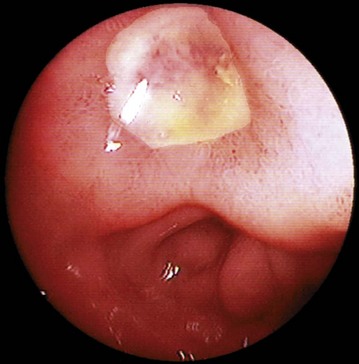

Benign gastric ulcers are typically regular in outline with a base consisting of white fibrinous slough. The ulcer gives the impression of having been punched out of the gastric wall, and there is no heaping-up of the mucosal margin as seen in malignant ulcers. The surrounding mucosa is surprisingly normal, although there may be radiating folds resulting from chronic fibrotic contractures. The typical endoscopic appearance of a gastric ulcer is shown in Figure 21.5a.

Fig. 21.5 Peptic ulcers

(a) Lesser curve benign gastric ulcer as seen through a gastroscope. At the original examination, the ulcer could be viewed from several directions and biopsies taken of the edge to exclude malignancy. (b) Photograph taken at emergency laparotomy for bleeding duodenal ulcer. The pylorus has been opened longitudinally and a deep chronic posterior ulcer crater is identified (arrowed). Thrombus T overlying an eroded artery is visible. A bleeding artery in the ulcer crater was under-run with sutures to arrest the haemorrhage